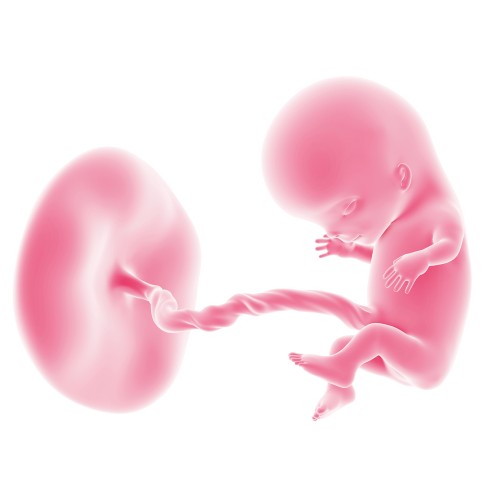

Развитие плода

11-я неделя беременности

11-я неделя беременности — важный этап, когда ребенок завершает эмбриональную стадию и начинает активно расти. Все органы и системы уже сформированы, но негативные внешние факторы могут повлиять на развитие плода. На одиннадцатой неделе длина малыша достигает 45-60 мм, а его вес составляет примерно 8 г.

Малыш становится все более похожим на человека, хотя его ручки пока значительно длиннее ножек. Голова остается непропорционально большой из-за активного развития головного мозга и формирования его основных отделов. Шея малыша продолжает удлиняться, что позволяет ему поднимать и поворачивать голову, меняя ощущения в животе на сроке 11 недель беременности.

У плода развиваются хватательный и сосательный рефлексы, а благодаря сосочкам на языке он уже способен ощущать вкус амниотической жидкости. Завершается формирование диафрагмы, что может приводить к икоте, хотя будущая мама пока этого не ощущает.

У мальчиков начинают формироваться половые органы, и при проведении ультразвукового исследования врач может определить пол ребенка, но для этого требуется высокочувствительный УЗИ-аппарат. Лицо плода продолжает развиваться, а в глазах появляются первые признаки радужной оболочки.

На 11-й неделе беременности продолжается рост и развитие всех внутренних органов. Печень активно вырабатывает кровь, а почки начинают производить мочу. Ребенок регулярно мочится в амниотическую жидкость, которая постоянно обновляется и выводится из организма с помощью плаценты и почек матери.

Многие внутренние органы начинают функционировать: желчный пузырь вырабатывает желчь, спинной мозг начинает производить эритроциты, гипофиз синтезирует гормоны, а печень образует белки, которые активно участвуют в формировании всех органов и систем малыша.